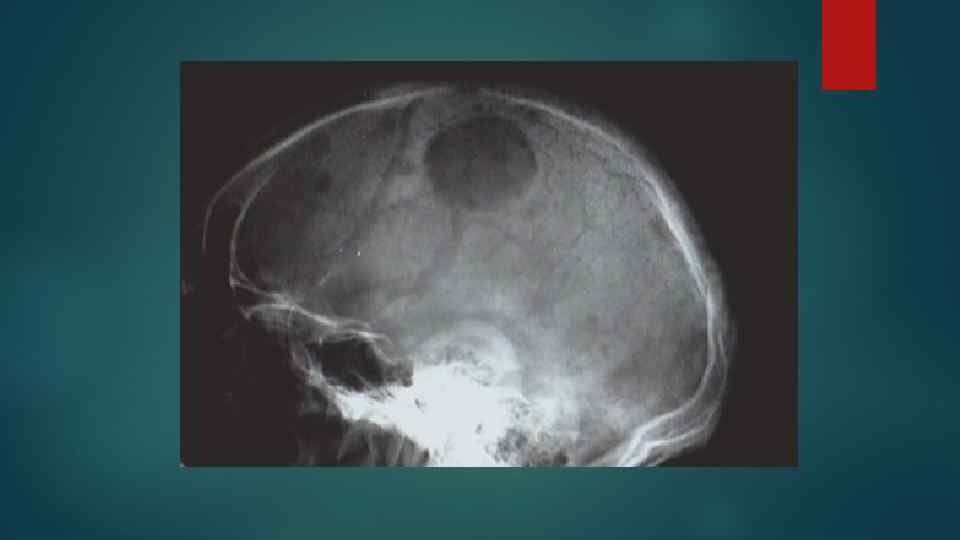

Проявления нейролейкоза Лейкемическая инфильтрация мозговой оболочки. мягкой Локолизация: паутинная оболочка, вирхов– робеновские пространства.

Лейкемические инфильтраты окружают сосуды, блокируют пути ликворооттока внутричерепная гипертензия. В ликворе выявляются бласты.